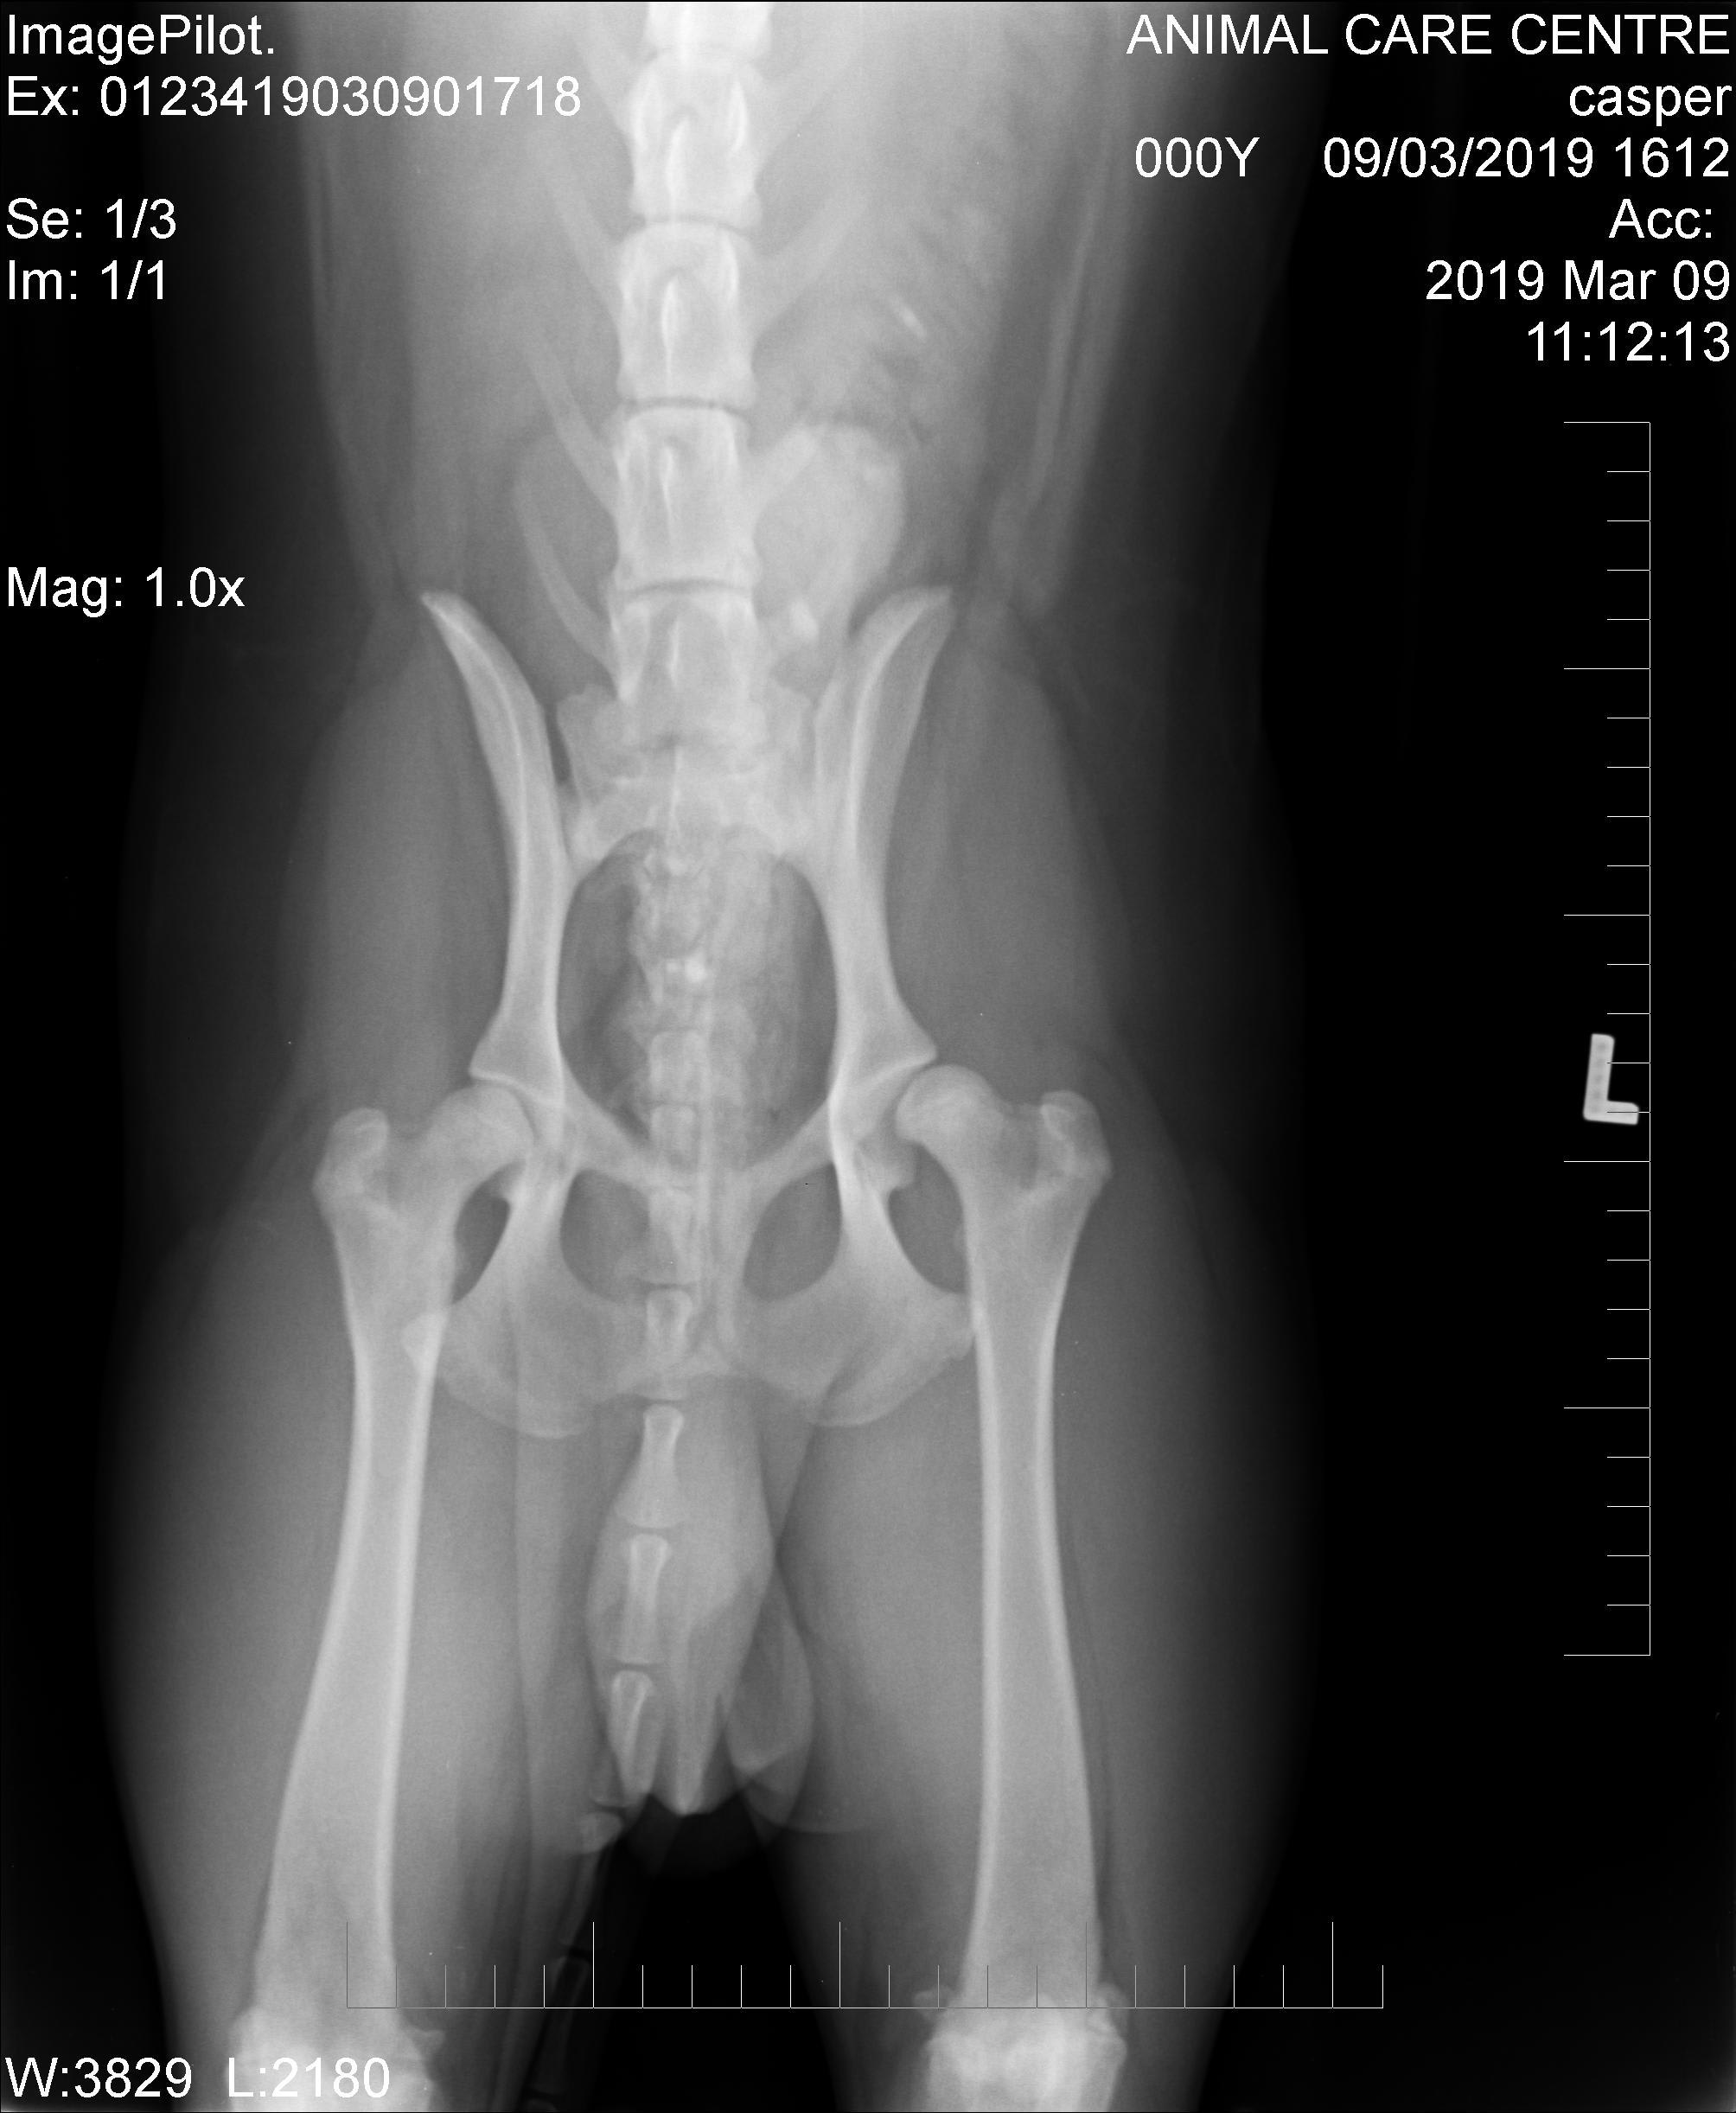

Hello. Yes, Casper does have hip dysplasia in the left coxofemoral (hip) joint. Just compare the two hip joints & you can see how much tighter the ball & socket fit together on the right side & how loose the left hip looks. Thanks for using Petco Pet Education Center, formerly Petcoach.